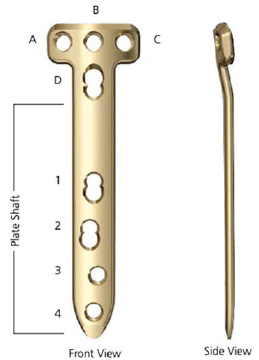

O implante indicado na figura é usado para realização da osteotomia

Essa figura mostra um exemplo de implante para osteotomia